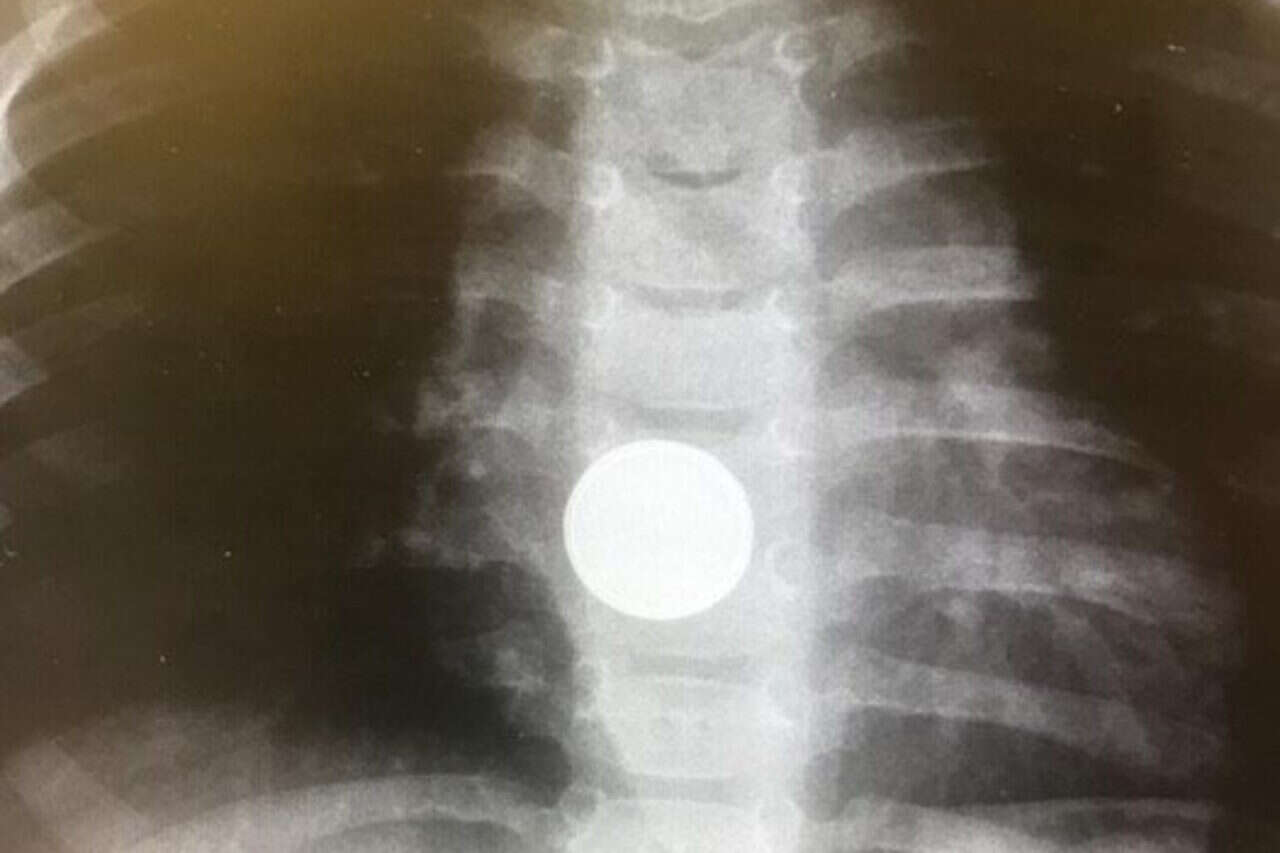

מה חדש? סוללה בדבש: בליעת חפצים קטנים על ידי פעוטות היא אחד הסיוטים של כל הורה, ובפרט בליעה של סוללות. הן עלולות להתפרק בדרכי העיכול ולגרום כווייה כימית ואף נזקים פנימיים לרקמות, בשל המוליכות שלהן.

בבית החולים שערי צדק גיבשו הנחיה מפתיעה שעשויה להמתיק מעט את המצב, ולא רק בראש השנה: לילדים מעל גיל שנה, שבלעו סוללה, יש לתת דבש מייד, על מנת לעכב ואף למנוע התפתחות של סיבוכים, זאת במקביל לפינוי מהיר אל בית החולים.

ההנחיה גובשה בעקבות פרסום מאמרים מקצועיים ומחקרים מהעת האחרונה, שהראו כי אכילת דבש מייד לאחר בליעה הסוללה עשויה לעכב היווצרות של כוויות כימיות, כיבים ופגיעה ברקמות, שנוצרים בעקבות המוליכות החשמלית של הסוללה והמגע ההדוק שלה עם דפנות הוושט. ההנחיה החדשה ממליצה להתחיל את הטיפול כבר בבית, במתן הדבש, ולגשת מייד למיון לקבלת טיפול בסמיכות לאירוע, כדי למנוע נזקים פנימיים קשים.

בשערי צדק מדגישים כי מתן דבש לתינוקות מתחת לגיל שנה אינו מומלץ גם במקרה של בליעת סוללות, משום שהוא עלול לגרום שיתוק נוירולוגי. לפי ההנחיה בשערי צדק, כל פעוט מעל גיל שנה יקבל 2-1 כפיות דבש בכל חמש דקות לאחר שבלע סוללה, עד להוצאתה דרך הלוע או בניתוח.

"בליעת סוללה על ידי ילד היא לא אירוע נדיר", מסביר ד"ר אורן לדר, מומחה בכיר בגסטרו־ילדים ואחראי על פעולות אנדוסקופיות בילדים בשערי צדק, "סוללה היא אחד הגופים הכי מסוכנים, והנזק עלול להיות קטלני. הדבר הקריטי ביותר הוא לשלוף את הסוללה כמה שיותר מהר. ועד שמגיעים לבית החולים אנו ממליצים לתת דבש להפחתת הנזק".